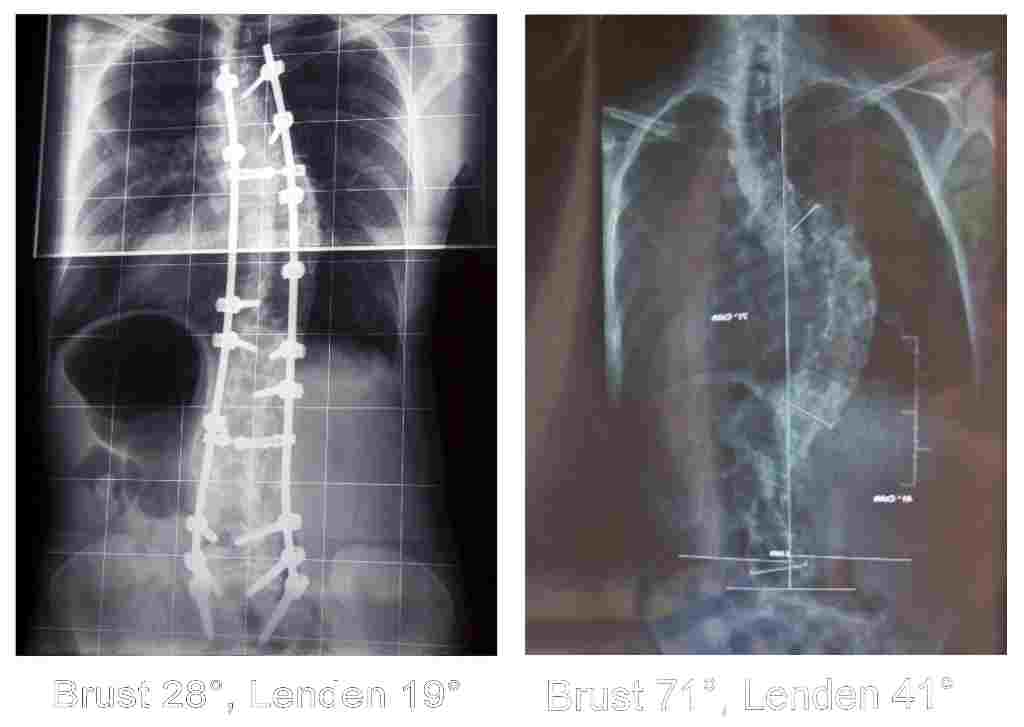

Habe gerade Eure Erfahrungen gelesen und es freut mich, dass es bei den meisten die OP gut geklappt hat. Meine OP war im Oktober 2007, es wurde von TH4 bis S1 mittels 2 Stäbe und 22 Schrauben versteift (AKH Wien). An und für sich habe ich keine Probleme, abgesehen davon, dass ich etwas beim Atmen eingeschränkt bin (als hätte mich etwas gehalten, einen vollen Atemzug zu nehmen) - dabei muss ich erwähnen, dass man mir bei der OP 7 Rippen gekürzt bzw. abgenommen hat. Vorher hatte ich 71° in der BWS und 41 in der LWS, jetzt ist es auf 28° BWS und 19 im Lendenbereich korrigiert. Irgendwie habe ich den Eindruck, je mehr Zeit vergeht, dass sich mein vorderer Rippenbuckel vergrössert... Ausserdem habe ich immer noch, und das nach fast 2 Jahren, das komische Gefühl am Rücken, als hätte ich einen Panzer, den ich auch bei jedem Atemzug und jeder Bewegung spüre (ohne Schmerzen jedoch). Das grösste Problem sind aber die Schrauben - die im Brustbereich, zuerst 3, kamen sehr bald nach der OP zum Vorschein, jetzt sind es schon 5, wobei sie sich, laut Röntgenbildern, nicht bewegen, dh. sie sitzen fest. Das hindert mich beim Sitzen (habe immer ein aufblasbares Polster mit), manchmal beim Liegen, wenn die Oberfläche nicht genug weich ist. Dazu kommt es, dass sie auch durch mein T-Shirt zu sehen sind, wenn ich mich nur ein wenig wo anlehne oder bücke... Auf jeden Fall ist es nicht schön und auch nicht besonders bequem...

Hat jemand von Euch ähnliche Erfahrungen? Hat man mir zu grosse Schrauben (gibts anscheinend welche für Kinder und für Erwachsene, die für Kinder werden bsw. in Japan für Erwachsene verwendet, da dort die Menschen eher zierlich sind)? Wär´s sinnvoll, das Gestell entfernen zu lassen? Meine OP war sehr schwer, sehr lang (fast 9 Stunden) und ich landete nachher auf der Intensivstation für eine Woche, weil meine Lunge nicht gut arbeitete (Vermutung war, dass sich dort Wasser ansammelte). Nach einem Monat habe ich das KH verlassen. Ich bin sonst gut zu Fuß, fahre Fahrrad, mache meinen Haushalt, eigentlich fast Alles, nur laufen kann ich nicht, da geht mir einfach die Luft aus und auch fühle ich mich viel zu steif dazu... Bitte um Antworten, hier meine Schrauben auf 2 Fotos, vor ca. 1/2 Jahr fotographiert.

Vergleich Vor und Nach.jpg

Vor und nach der OP

(26.58 KiB) 1455-mal heruntergeladen